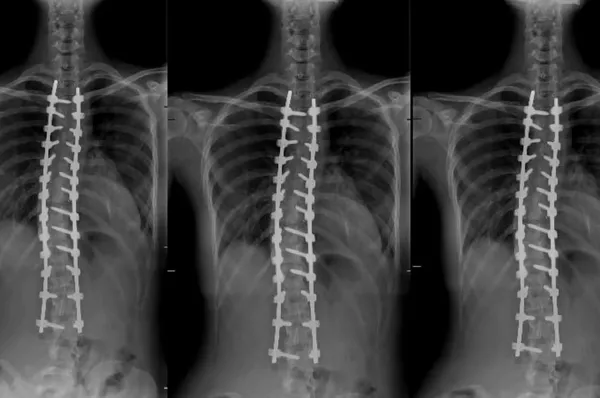

Aleksandra'nın kendilerine skolyoz şikâyetiyle geldiğini belirten Opr. Dr. Yunus Uysal, "Rusya'dan bize filmlerini gönderdiğinde omurgasında yaklaşık 60 derecelik bir eğriliği vardı. Ameliyat olması gerektiğini ilettik. Bizim önerimiz doğrultusundan Rusya'dan Türkiye'ye geldi. Burayı tercih etmesinin sebebi, Türkiye'deki tıp uygulamalarının üst seviyede olması olmuş. Kurumumuzda mevcut olan robotik omurga cerrahisini tekniğinden faydalanarak skolyoz ameliyatını gerçekleştirdik. Ameliyattan önce 60 derece olan eğriliği, neredeyse '0' derecesine kadar düzelttik ve yüz güldürücü bir sonuç aldık" diye konuştu.